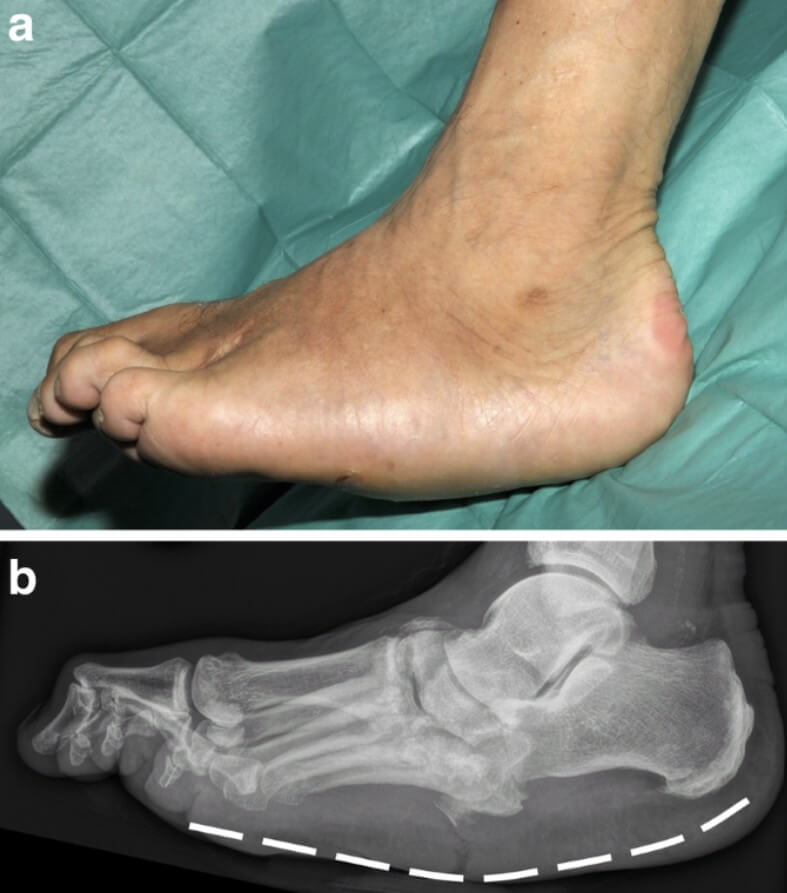

Tempat Pengobatan Anak Autis di Jakarta dan Pekanbaru - Jawabannya yaitu Anda bisa meminimalisir hingga mencegah dari charcot joint atau sendi charcot. Apa saja yang menjadi tanda awal ketika Anda menderita charcot joint atau sendi charcot? Dimulai dari kaki bengkak, kulit pada kaki menjadi merah, hangat tanpa cedera yang jelas.

Hal ini perlu diagnosa dan tentunya penanganan secara cepat, agar tidak memperparah kondisi bagian kaki.